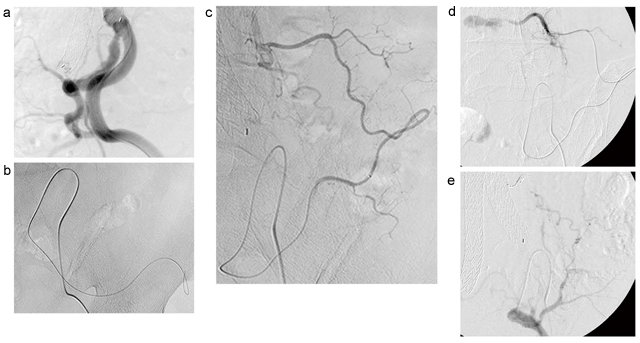

まず,左総大腿動脈からショートシース(3Fr.システム対応)を挿入。左内腸骨動脈の分岐形態を,右前斜位35°で造影し確認した(図5 a)。シェファードフック型の親カテーテル(3.5Fr.)を用い,左内腸骨動脈を選択,ガイドワイヤを左上殿動脈の奥まで進め(図5 b),コブラ型の親カテーテル(3.5Fr.)に交換。親カテーテル・マイクロカテーテル(2.0/2.4Fr.)を左腸腰動脈に挿入,造影にて経路を確認した(図5 c)。超選択的CTAで確認した血管走行・形態であった。さらにマイクロカテーテルを慎重に進めていき,左第4腰動脈に到達した(図5 d)。離脱式コイルを計4本留置し,血流遮断を確認した(図5 e)。

図5 TAE時の血管造影画像

a:右前斜位で造影した左内腸骨動脈 b:ガイドワイヤを左上殿動脈に挿入

c:正面で造影した左腸腰動脈 d:マイクロカテーテルが左第4腰動脈に到達 e:TAE後に造影した左腸腰動脈